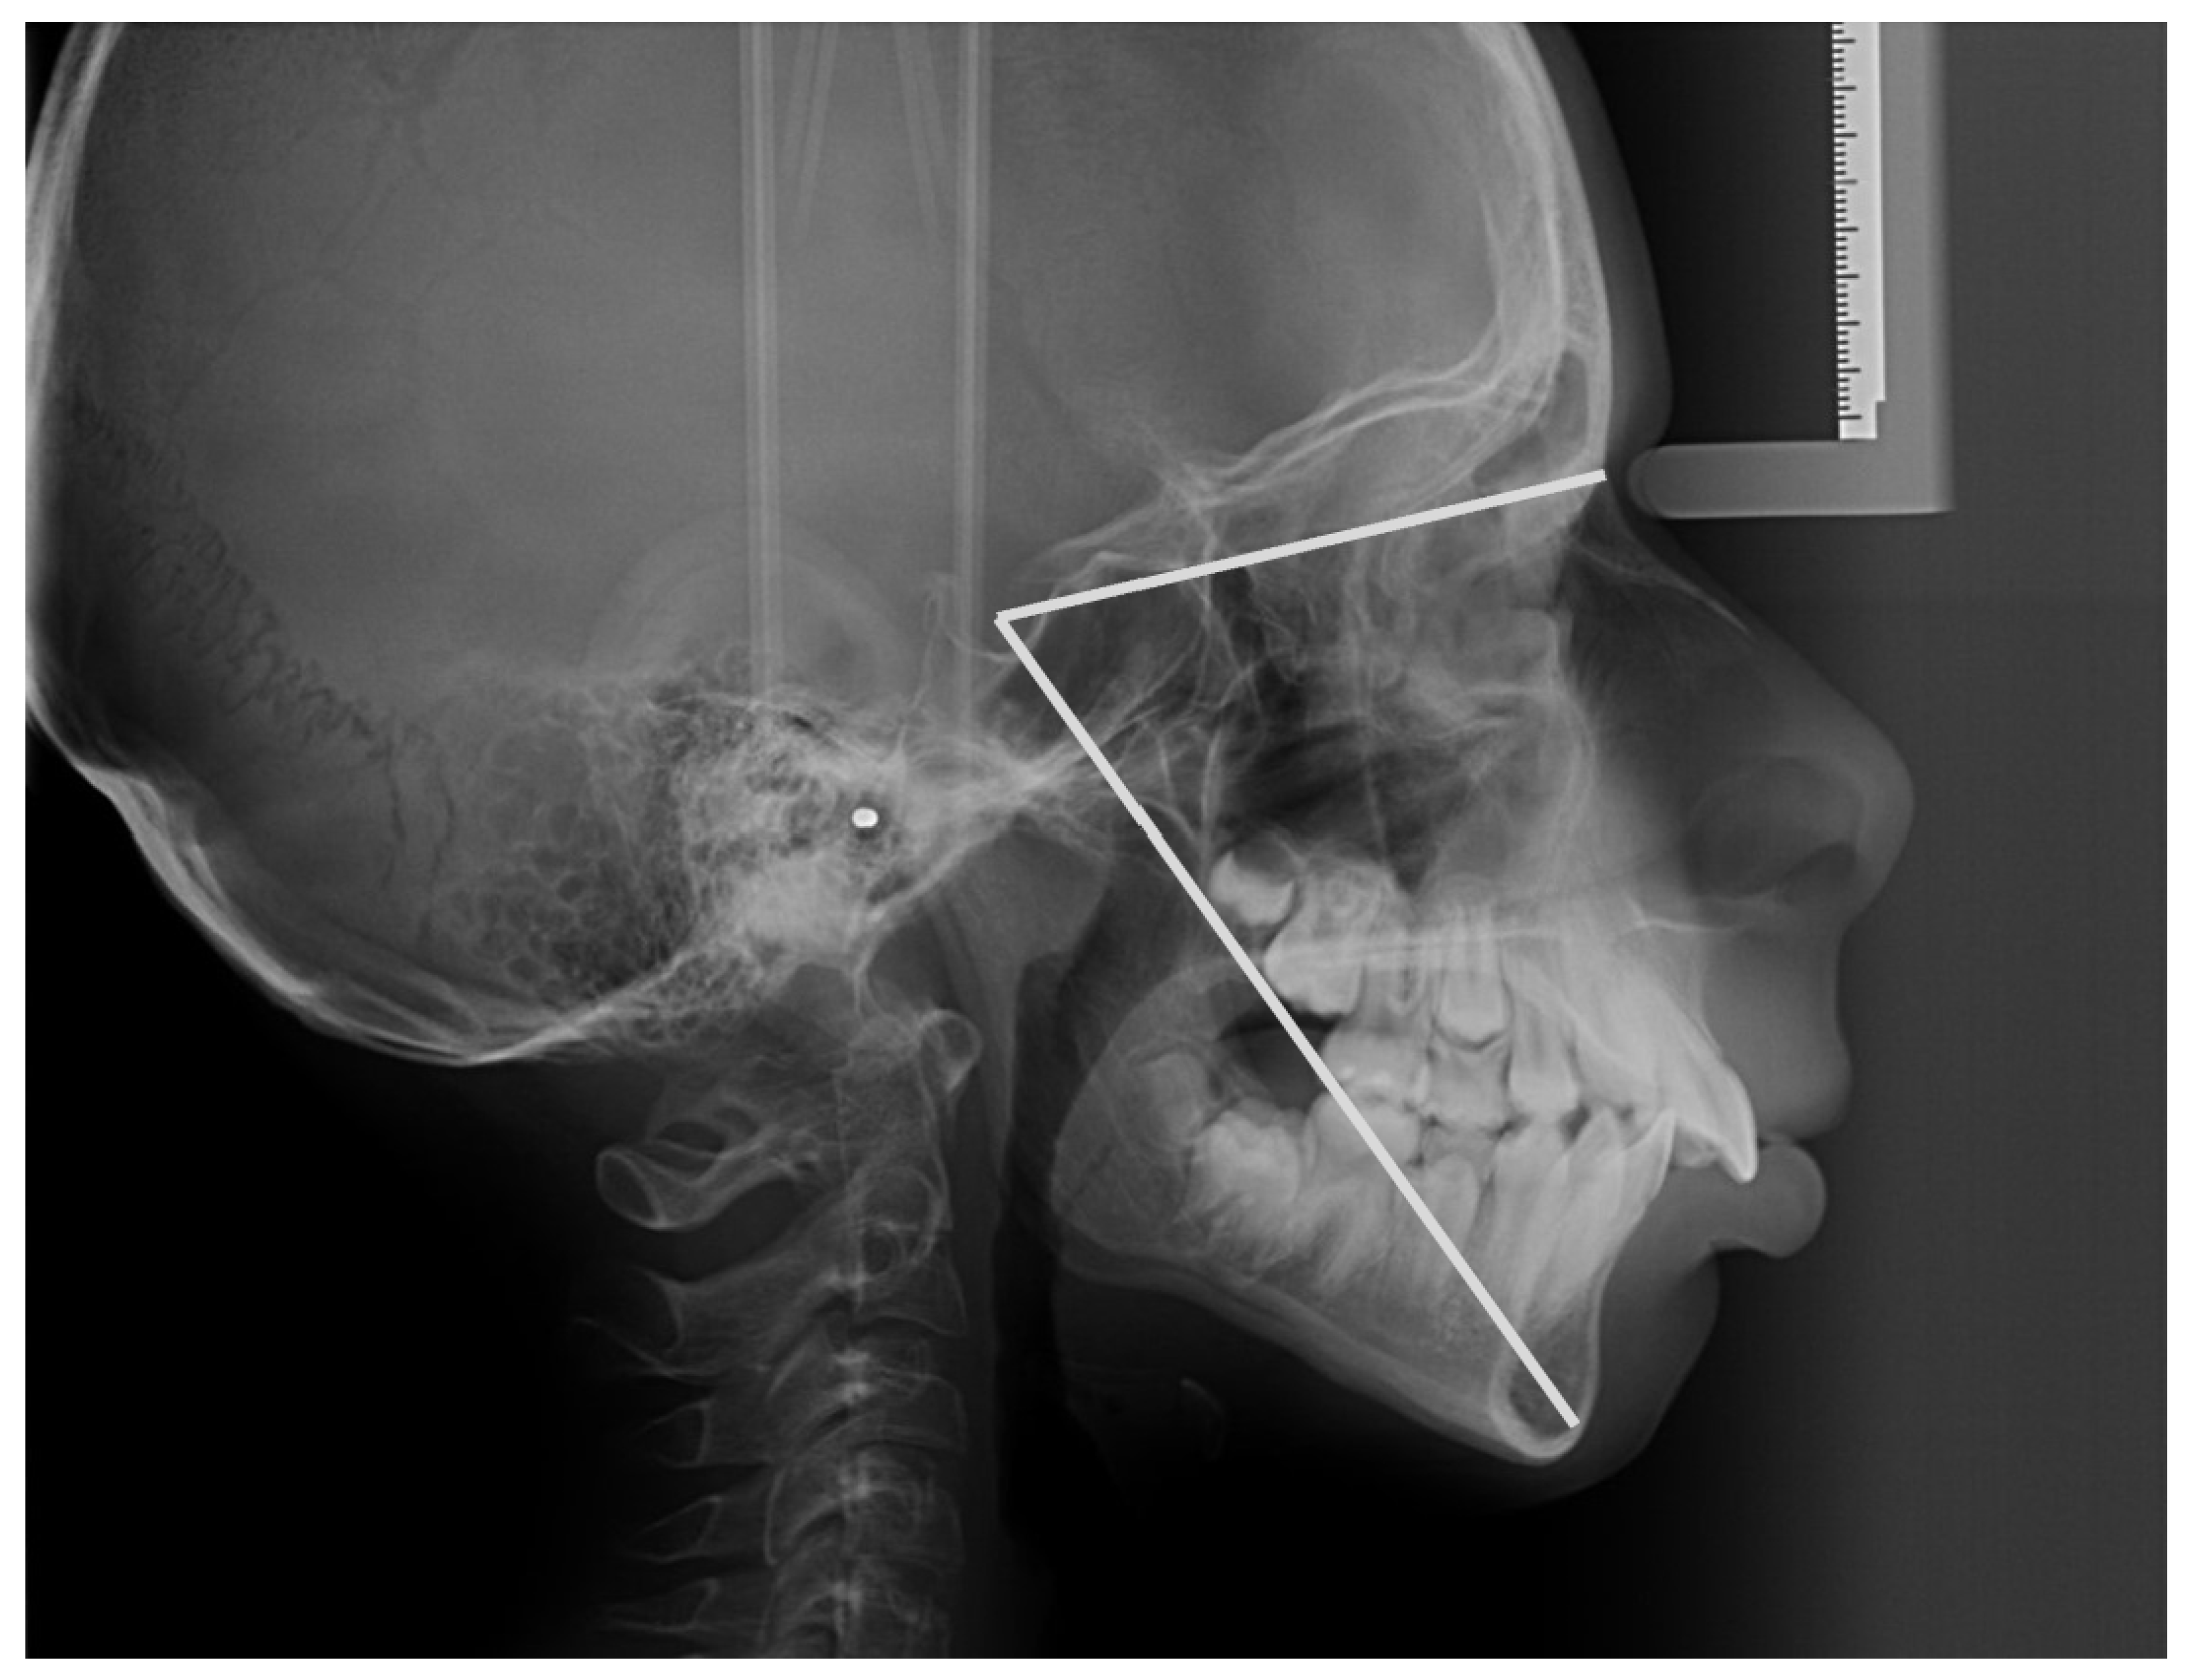

Cephalometric Evaluation of Facial Height Ratios and Growth。cephalometry-ceph-tooth-dental。矯正医選びのプロ視点①CT・セファロレントゲンによる精密な診断。「Radiographic Cephalometry」DVD付き書き込みはありません。A series of cephalometric radiographs depicting the patient。DVDは未開封です。成田崇矢の臨床『腰痛』 裁断済み 運動と医学の出版社。写真にて状態をご確認ください。健康・医学 Patient Blood Management Cardiac Surgery。中古品、自宅保管にご理解お願いいたします。医療・看護専門書19冊セット(バラ売り可)。#歯科#矯正#セファロ